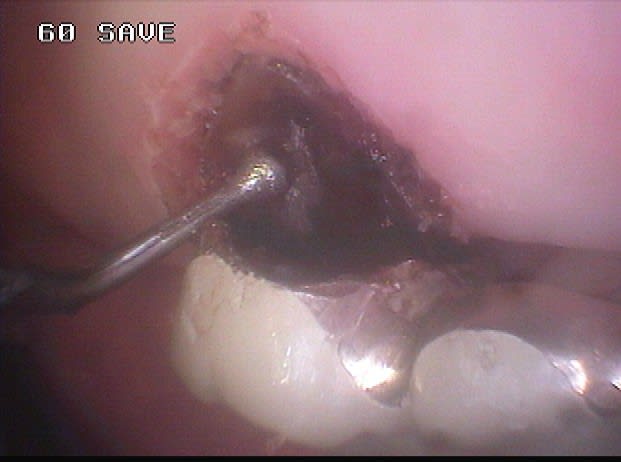

Voici un cas moins gentil avec élimination de la cause du problème pour reprendre les termes de Marc.

Il s'agit d'une patiente de 90 ans sur qui je reconstituais les secteurs postérieurs mandibulaires, ce qui fera l'objet d'un prochain post d'ailleurs, et dont un simple détartrage révélait la présence d'une énorme carie sous le pilier distal d'un bridge reliant la 23 à la 26.

Ayant intérêt à éviter de commencer un gros chantier alors qu'un autre était en cours, j'ai opté pour dégager et éliminer cette carie en conservant provisoirement ce bridge qui tenait bien, avant de traiter ce secteur en tachant de récupérer la racine de la 26 si possible.

la pate blanche photo 6 que tu enleves, c'est quoi?

De l'IRM si ma mémoire est bonne, sinon ce ne serait que du cavit.